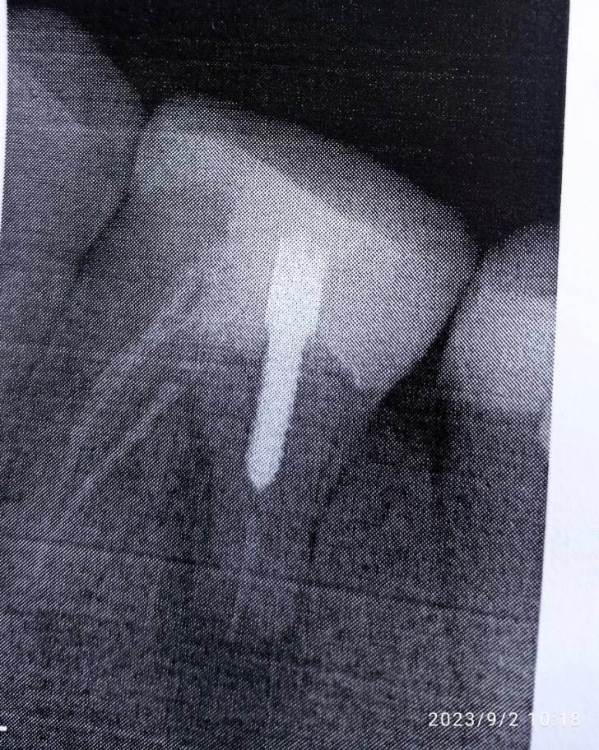

Iris11 Опубликовано 8 сентября, 2023 Автор Поделиться Опубликовано 8 сентября, 2023 Не знаю, почему врач оставил зуб открытым. Сегодня сделали снимок повторно. Говорит, что гной не вышел зуб нужно удалять. Подскажите, совсем никак не спасти? Под коронку никак ? Ссылка на комментарий

Iris11 Опубликовано 8 сентября, 2023 Автор Поделиться Опубликовано 8 сентября, 2023 Хочу сейчас к другому стоматологу пойти. Получается нельзя было зуб открытым оставлять. Врач сказала, просто полоскать содой и солью каждый час. Ссылка на комментарий

Carioznik Опубликовано 10 сентября, 2023 Поделиться Опубликовано 10 сентября, 2023 08.09.2023 в 17:10, Iris11 сказал: почему врач оставил зуб открытым Такой метод широко применялся ранее. Сейчас так лучше (по возможности) не делать, есть более правильные методы лечения. 08.09.2023 в 17:10, Iris11 сказал: Говорит, что гной не вышел зуб нужно удалять. Не факт, но процент неудачи ближайшей или отдаленной в Вашем случае не маленький. 08.09.2023 в 17:10, Iris11 сказал: совсем никак не спасти? Можно, но сначала нужна хорошая диагностика для определения прогноза лечения, далее- врач должен обладать достаточными мануальными навыками (например, лечение под микроскопом этого зуба является важным условием: качественно запломбировать один из корней зуба без увеличения - будет ,наверное ,невозможно, но и не только в этом дело...). Ищите врача специализирующегося на лечении каналов (он будет работать с микроскопом по умолчанию). Но будьте готовы к тому, что и он может "забраковать" этот зуб либо до, либо в процессе лечения. 1 Ссылка на комментарий

Iris11 Опубликовано 12 сентября, 2023 Автор Поделиться Опубликовано 12 сентября, 2023 Сходил, другому стоматологу. Был сделан 3D снимок. Вердикт врача - удаление т.к корень частично растворился. Зуб удалили. Потом я узнал, что можно сохранять 2-х корневой зуб с одним корнем. Хочется узнать, действитель ли это возможно? Ссылка на комментарий